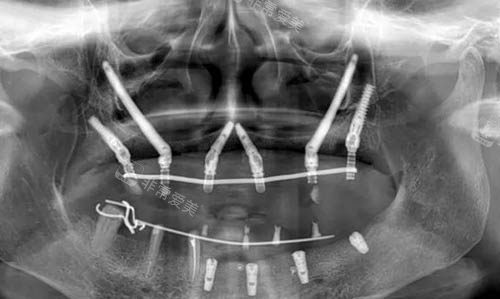

穿颧穿翼种植ct照片

穿颧穿翼种植是针对牙槽骨重度萎缩(尤其是上颌骨)的“高难度技术”,很多机构不敢做,但凯尔口腔已积累不少成功病例:

技术成熟,适应范围广:传统种植需要足够牙槽骨,穿颧穿翼则直接将植体植入颧骨或翼板,即使骨量不足也能稳定固位,适合半口/全口缺失、牙槽骨吸收重度的患者。